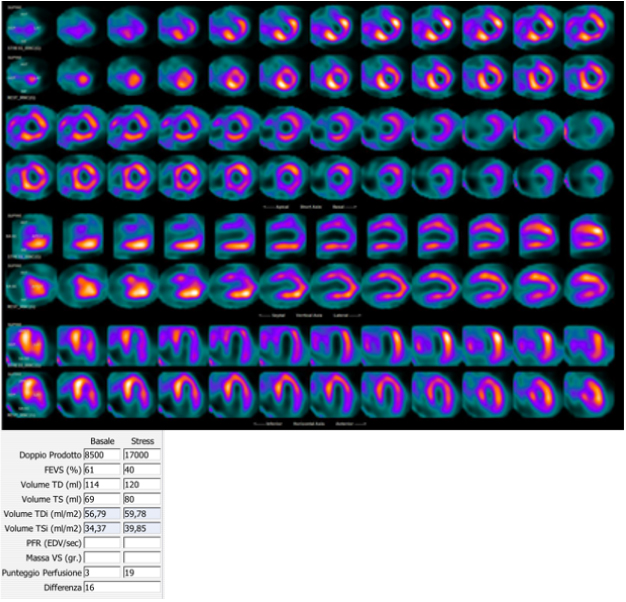

Fig. 2.Coronary angiography images of the case described in Fig. 1 showing diffuse CAD, with severe stenosis of the left main artery. Left: right coronary artery; Right: left main, anterior descendent and circumflex arteries.